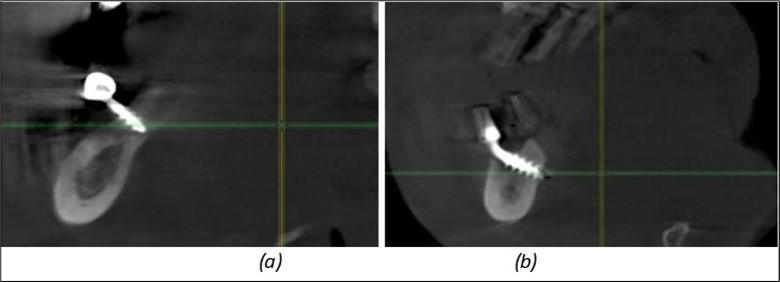

Figure 13.Corticobasal BCS implants fixed between the vestibular and lingual cortices with support on the basal bone: (a) BCS fixed between the lateral cortices; (b) BCS implant with support on the basal cortex.

Figure 14.Rx panoramic final situation control: (a) Panoramic X-ray with the addition of a distal BCS implant in quadrant 3 at 11.2022; (b) Control X-ray, 10.2023.